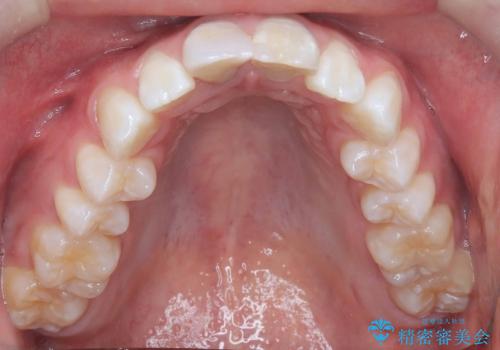

【ワイヤー矯正 11ヵ月で矯正終了!】歯のでこぼこを治したい!

- 「歯のでこぼこを治したい 1年くらいで矯正を終わらせたい」を主訴に来院された患者様です。

叢生量は多く無く歯の傾斜も標準傾斜だったので歯は抜かずにワイヤー矯正で治療を行いました。

左側は2級傾向が強く臼歯の遠心移動をご提案しましたが、1年以内に矯正を終わらせたいという患者様のご意向で希望されず叢生を改善する矯正となりました。